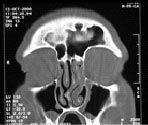

РентгенНосовые пазухи

КТНосовые пазухи